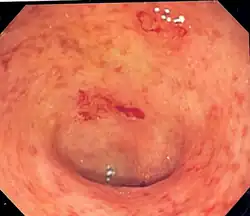

| Endoscopic image of a colon affected by ulcerative colitis. The internal surface of the colon is blotchy and broken in places. Mild-moderate disease. | |